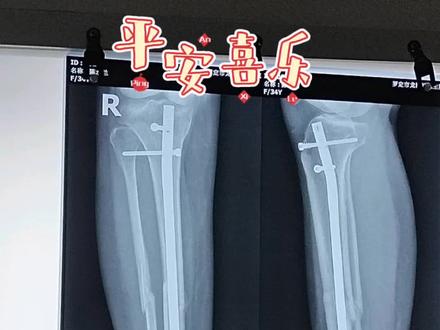

骨折的恢复需要复位、固定、功能、锻炼三个过程。骨折生长需要的条件是骨折局部良好,对位牢固固定,需要骨骼医生的各种专业处理,包括手法、复位、 手术、内外固定等。局部血运良好,没有感染。全身因素包括良好的营养、正常的血糖水平及内分泌环境。骨折恢复后期功能一般需要指导下锻炼才能完全正常。

大家好,我是骨骼大伟医生。今天呢,我们来谈谈骨折的愈合过程。正常骨折愈合过程分为四期,第一期是水肿气化形成期,一般是骨折后的两周之内。第二期是纤维性骨架,也就是软骨架形成期, 一般是骨折后的两到四周。第三期是原始骨架,也就是骨型骨架形成期,一般是骨折后的四到八周。第四期是骨架重塑,随墙再通起,一般是骨折后的八到十二周。请大家多多点赞关注。

骨折的愈合过程一般分为三个阶段,血肿激化、眼近期、原始骨加形成期、骨加改造塑形期。当人体发生骨折后,骨折部位在数小时内便开始修复, 血液在骨折部位凝固形成,血肿愈合便已悄悄开始。破骨细胞承担着人体骨骼的发育、生长、修复等功能。骨折后,破骨细胞开始清除坏死骨组织,在数周后,成骨细胞将加转化为骨, 不断的重塑和机械应力产生并塑造了新股。数月或数年后,骨骼恢复其原有的强度、形状和内部结构,骨折愈合完成。

一般来说呢,四到六周以后开始形成一些新生骨,但是比较啊脆的,或者是比较早期的, 嗯,只有在六到八周以后才能够产生一个稍微比较牢固的一些。呃骨,我们称之为新生的骨架,当然了更长的更更多部位呢,或者说更大的这个骨头可能需要两到三个月才能看到这些骨架的生长。 呃,不同部位的新生股,他的这个新生股的形成速度和啊形成的这个量的多少是不同的。 呃,因为你固定方式的不同啊,以及你有没有加入其他的康复饲料的方法,或者是药物的方法,也会导致这种啊新生活生长的速度不同。但总体来说呢, 骨折以后他经历过这么几个愈合决赛才能打成新生骨的形成。早期呢是一个血肿,也就是骨折端是有积血, 在积雪慢慢的积化以后,会在两个星期到四个星期之间呢,形成一些纤维组织,这些纤维组织在四周到八周时间会形成一些新生的骨,类似于早期的软骨, 所以在六周之前呢,大部分是一种新生的早期的软骨形式。当然在八周以后,也就是说两个月以后慢慢会形成一些稍微比较坚硬的,类似于早期骨的一种形态,我们称之为 骨架。这种骨架早期呢是比较大的,比较散乱的,他在后期呢会变成牢固的一种固定, 当然这种股价会在更长的时间里面呢,三个月到半年或者半年以上,他随着我们这个行走啊功能锻炼以及我们关键的活动而得以复行, 所以如果骨折以后,我们通过固定锻炼可以进到儿时的这个新生骨啊形成,并且是在塑形,这个时间取决于固定的方式、固定固定的部位以及功能康复的方式的不同而不同。

伤筋动骨一百天真的是这样吗?今天就给大家聊一下。骨折愈合的时间大致可分三个阶段。首先就是伤后两周内血肿形成期,这个阶段骨头是断开的,需要固定石膏也可以, 钢板也可以,否则就会错位。接下来就是初始愈合期,大约需要两个月,这阶段的骨折已经开始生长了, 只是并不十分牢靠,所以这个阶段可以适当的活动,只要不是错误的暴力的运动就行。第三个阶段就是骨架改造塑形期, 所谓伤筋动骨一百天,也是指这个阶段差不多达到了骨折临床愈合的标准。所以说这句话是有道理的。